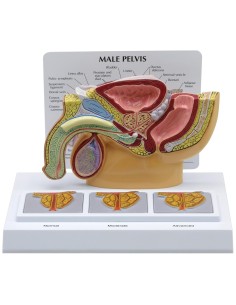

Pelvis masculin 3B Scientifique avec ligaments, vaisseaux, nerfs, plancher pelvien et...